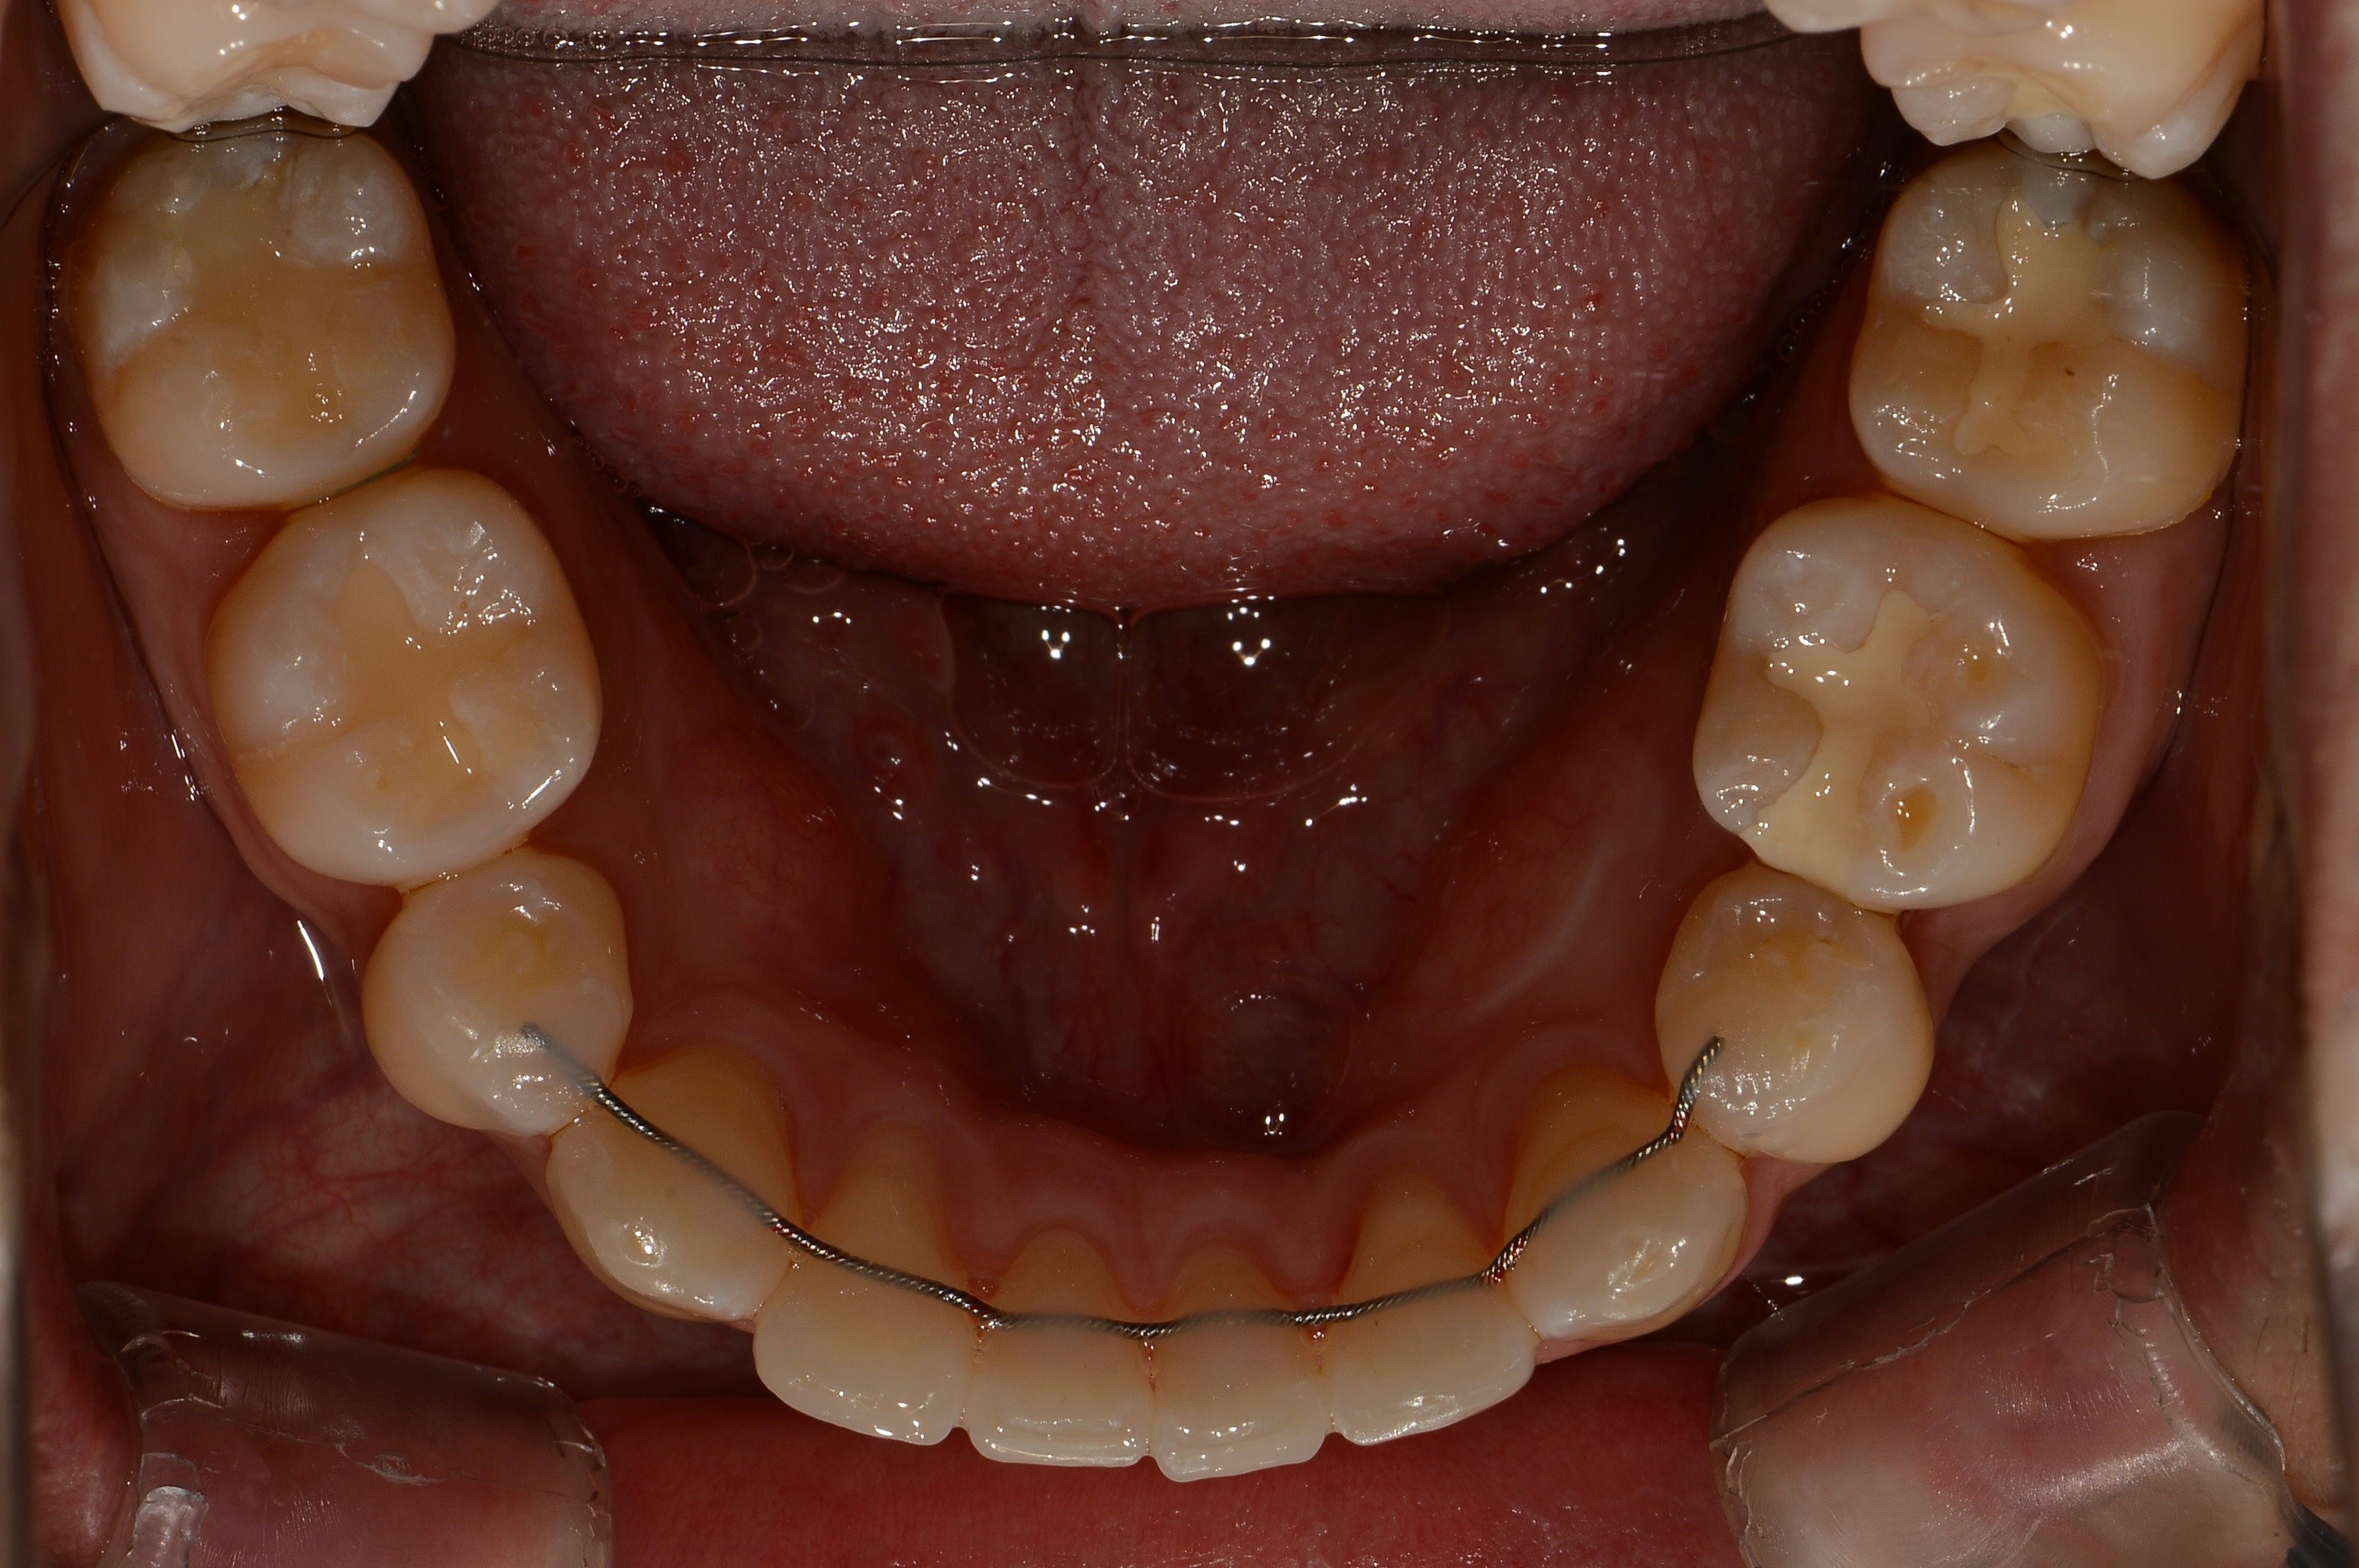

치료 전 사진입니다.